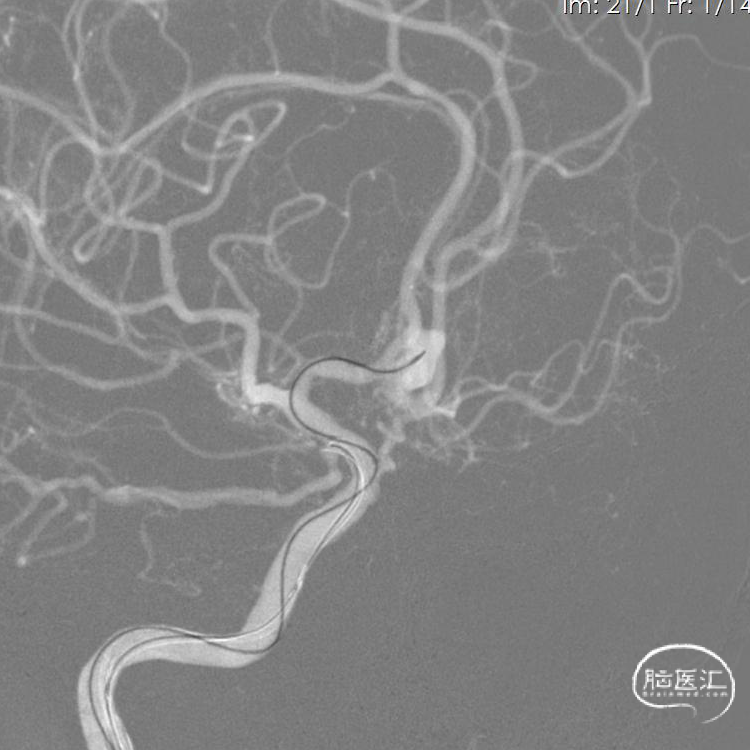

入院后完善术前准备于急诊全麻下行DSA。

1、右侧颈内动脉造影提示双侧大脑前动脉显影,前交通动脉可见动脉瘤。

2、行右侧压颈试验后左颈内动脉造影示左侧大脑前动脉未见显影。

3、行左椎动脉造影示左侧大脑前动脉供血区可见浅淡显影。

4、工作位测量:瘤颈长约3.94mm,瘤体大小约9.09×7.40mm,主瘤体上可见三个子瘤大小分别为:3.84×2.43mm、3.09×2.54mm、3.39×2.44mm。